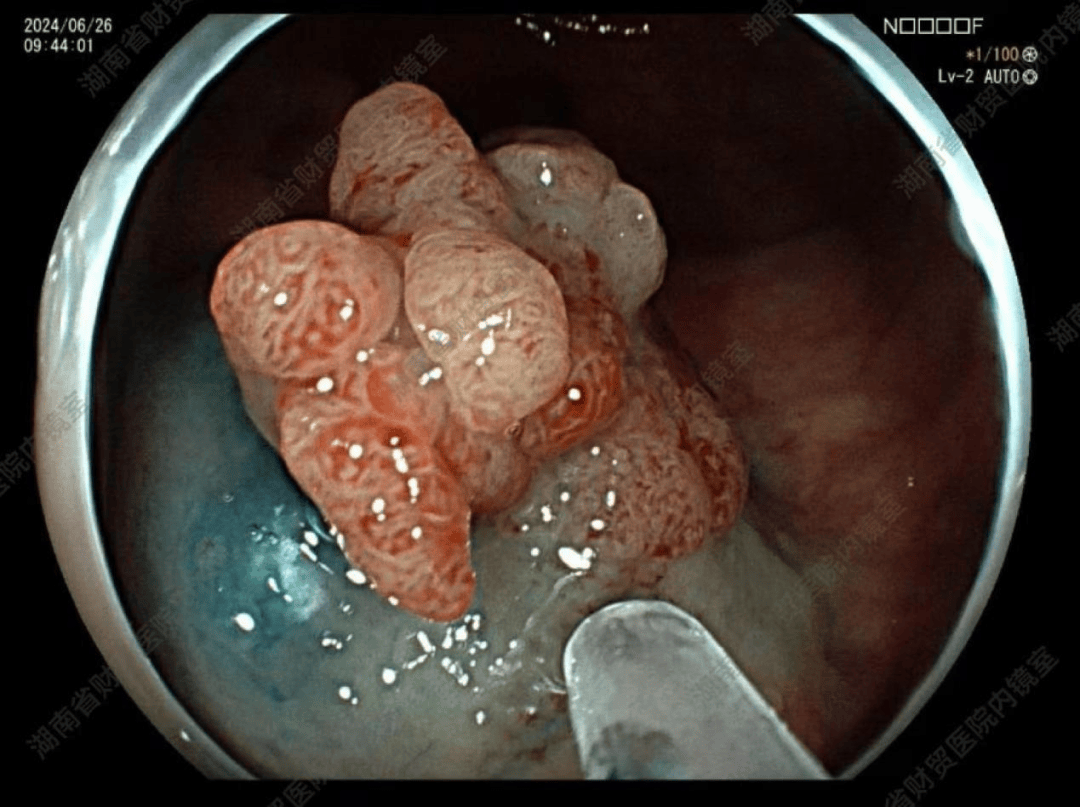

肠绒毛状腺瘤

5cm,病理提示绒毛管状腺瘤,属于癌变风险极高的类型,住院行内镜下病灶

结肠腺瘤(lst-g)esd--内镜新技术